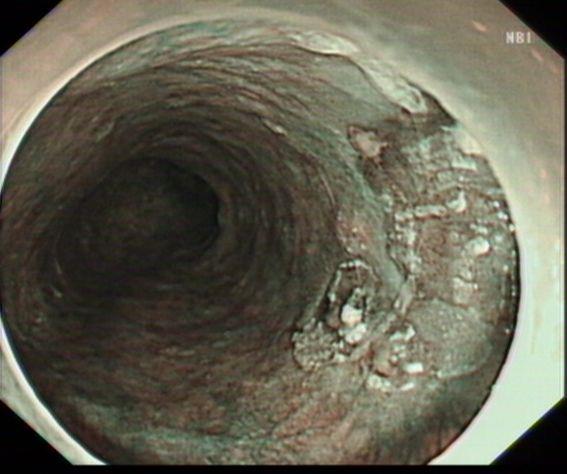

内镜NBI示:病变黏膜粗糙,呈茶褐色改变

以Dual刀行病灶周边标记